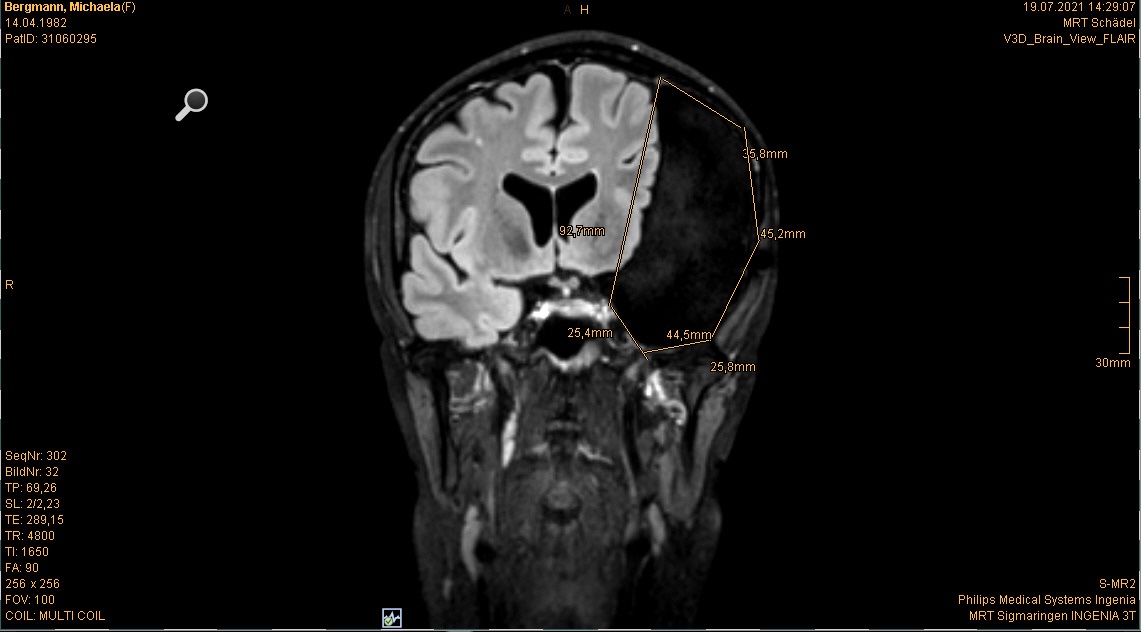

Im Juli stand ja auch noch mein jährliches Kopf MRT an. Ist ja schon quasi „same procedure as every year“. Es gab nichts überraschend Neues oder so. Wenn man es optimistisch sieht kann man sagen: Unverändert. Wenn man es realistisch sieht: gleich beschissen wie vorher

Für alle, die sich neu hier auf meinem Blog tummeln und schon an der ein oder anderen Stelle von meinem „Untermieter“ gelesen haben, sei er hier noch einmal mit den aktuellsten Bildern „vorgestellt“

Die Bilder sind also die aktuellsten vom 19.07.2021. Ja ich weiß, der ist ja riesig, ja ich weiß, dass das ja echt shit ist usw. usw. Aber das weiß ich nun schon seit dreizehn Jahren und ich habe mich damit arrangiert und abgefunden. Womit wir zum nächsten Gedankenthema kommen.

Es ist für mich ja nicht mehr schockierend, wenn ich die Bilder sehen, denn ich weiß ja was mich erwartet. Aber für den ein oder anderen Außenstehenden oder mich noch nicht kennenden Mitarbeiter in der Radiologie im Krankenhaus ist das doch schon immer wieder was Besonderes. Und als ich dieses Mal so den MRT Gang entlang schritt und herein gerufen wurde, wusste die eine Mitarbeiterin, dass ich nun schon zum 37sten Mal das ganze Prozedere über mich ergehen lasse und sagte dementsprechend nicht mehr viel zu mir (bzgl. alles mit Metall muss ausgezogen werden vorher, dann wird der Kopf mit einer Art Kopfkäfig fixiert, dass man ihn während der Aufnahmen nicht bewegt usw.). Es läuft alles wie eine Art Routine und im stillen Einvernehmen zwischen uns ab. Der andere Mitarbeiter der da war, war sichtlich irritiert. Und wollte mir zuvorkommen und mich aufklären, wusste aber auch nicht ob er das, weil seine Kollegin (wohl auch seine Vorgesetzte) schwieg, irgendwie nicht richtig wäre usw. Während ich dann immer so im MRT liege und die Bilder gemacht werden (das dauert dann immer gut so zwanzig Minuten) gehen mir auch meist zig Sachen durch den Kopf. Ehrlich gesagt keinerlei Gedanken bzgl. des MRTs selbst, sondern eher bzgl. dem was seit meinem letzten Besuch hier mal wieder alles so los war und passierte.